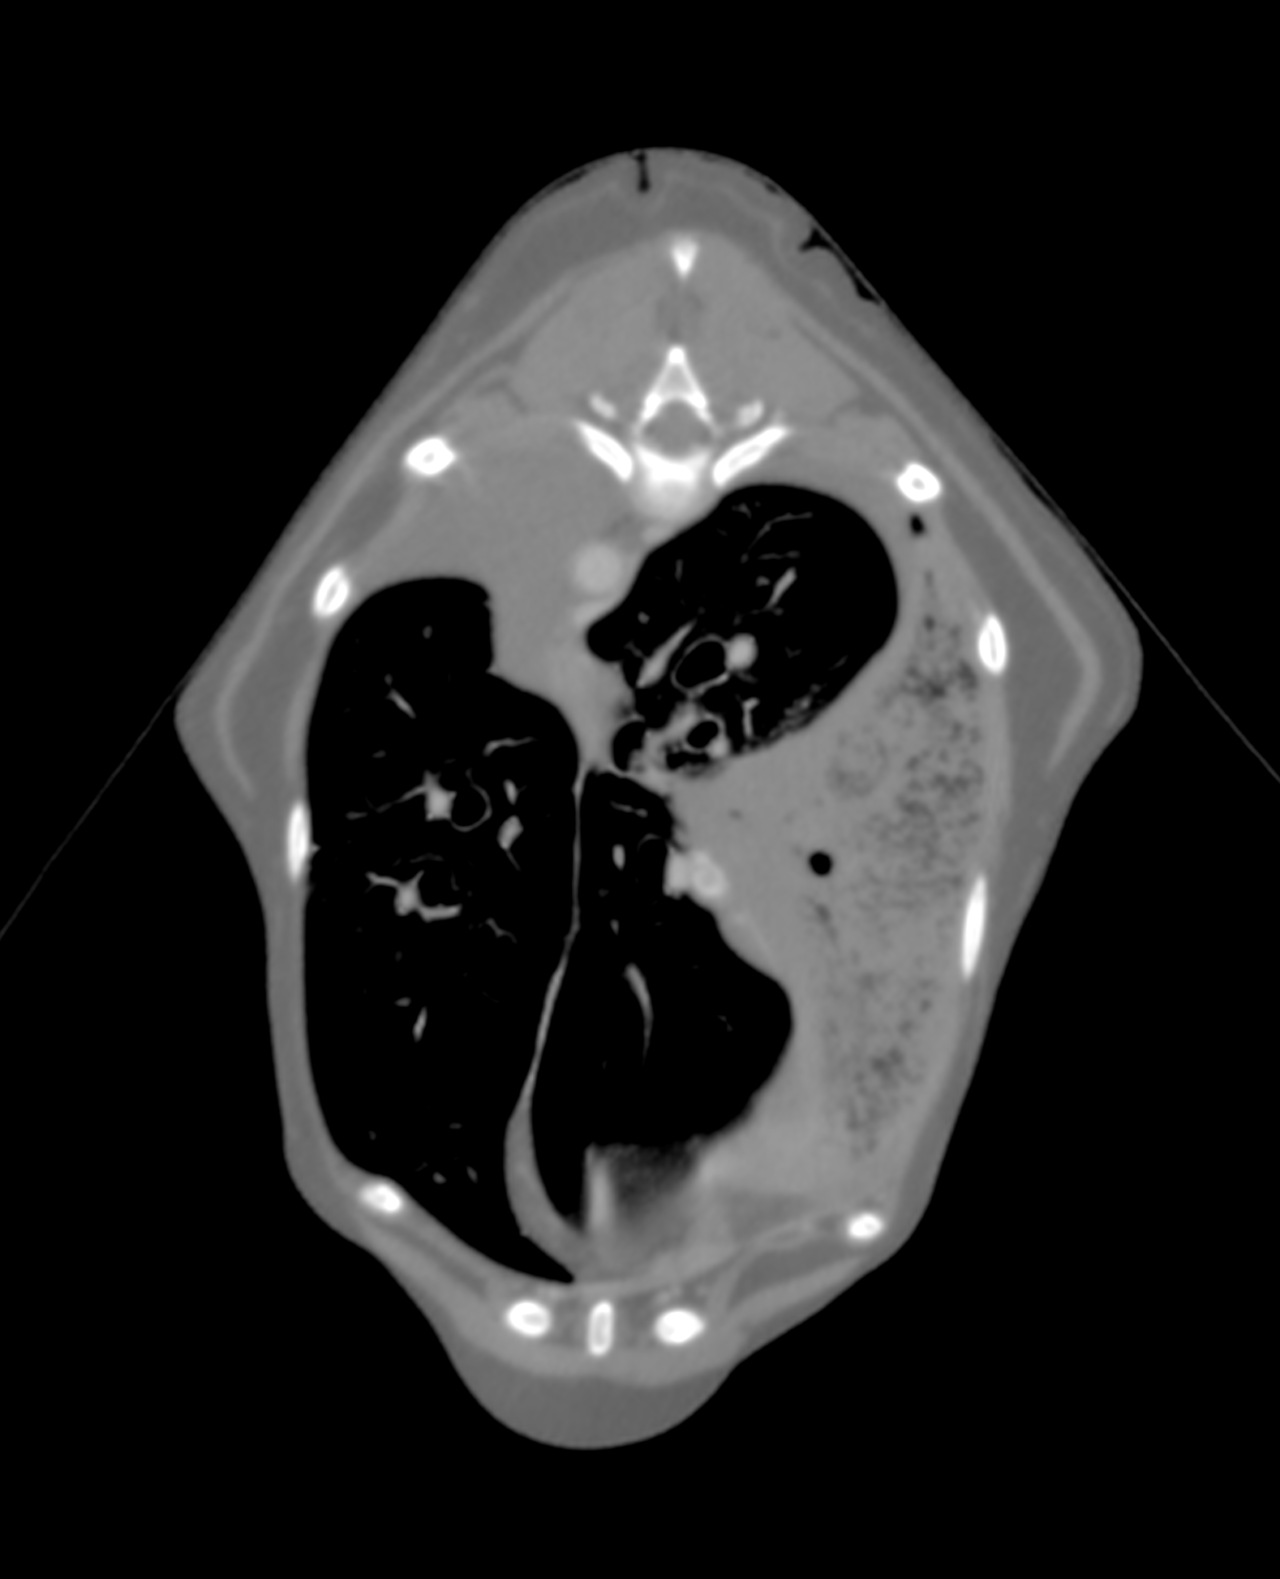

14歳のイタリアングレーハウンドが主訴として発咳を呈し、CT検査により左右両側の肺葉捻転が疑われた。肺葉捻転は稀であり、特に左右両側で発生することは極めて珍しい。左右肋間開胸術を実施して肺葉切除を行った。手術ではTA30Vステープラーを使用し、迅速かつ安全に肺葉切除が行われた。術後の経過は極めて良好であり、術後5日目には退院が可能となった。高齢犬でありながら、迅速な診断と適切な外科的介入が回復に寄与した。左右両側の肺葉捻転は非常に稀なケースであり、この症例は早期診断と外科的治療の重要性を示している。特にCTによる正確な診断と、適切な外科器具の使用が良好な術後経過につながった。肺葉捻転は自然発生的に、または乳び胸、外傷、腫瘍、慢性呼吸器疾患、あるいは過去の胸部外科手術などに伴って起こる。イヌの肺葉捻転は右中葉がもっとも多く(43%)、ついで左前葉に多く(35%)に起こることが報告されており、胸の深い犬種では右中葉に、小型犬種では左前葉に捻転が起こりやすいとされている。複数の肺葉に捻転が見られたことは稀である。